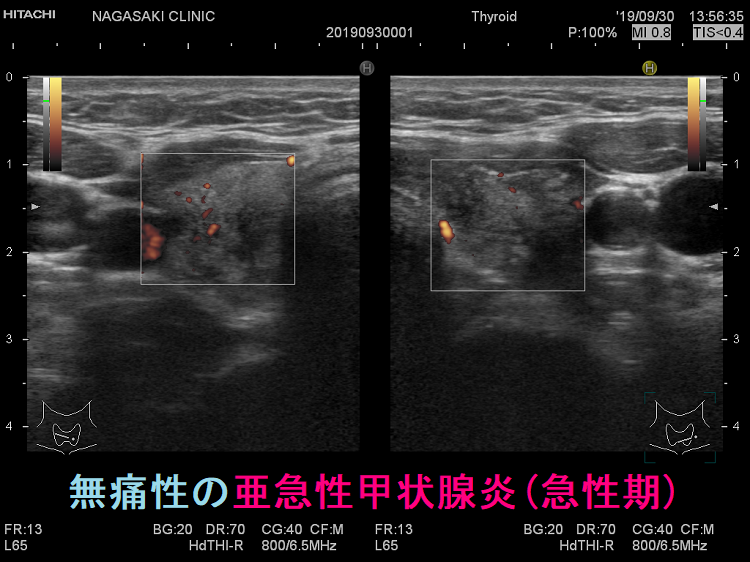

亜急性甲状腺炎の頚部痛は千差万別です。まるで痛風のごとく、触れただけで飛び上がるような痛み、蚊に刺されたほどの痛み、無痛性の場合もあります。(Thyroid. 2001 Jul;11(7):691-5.)

頸部痛を伴わない無痛性亜急性甲状腺炎(painless subacute thyroiditis)の頻度は全体の5-10%とされ、特に新型コロナウイルス感染後の報告が増えています。[Cureus. 2022 Jul 16;14(7):e26924.][Cureus. 2022 May 12;14(5):e24949.]

不思議な事に、無痛性であっても炎症が強かったり、甲状腺中毒症が強かったりします。元々、痛みに鈍感な高齢者や糖尿病患者でなくても無痛性の場合があります。

無痛性であっても、甲状腺超音波(エコー)所見はほぼ共通です。要するに、超音波(エコー)検査で即診断。